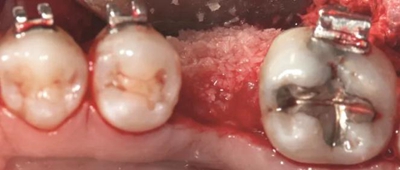

圖2c. 移植處用膠原膜保護,磨牙后區(qū)用硫酸鈣覆蓋

圖2d. 3個月后,獲得顯著的骨增量,同時創(chuàng)造出1.6mm的近遠中修復空間

翻起頰側(cè)瓣后,放置同種異體凍干骨(freeze-dried bone allograft,F(xiàn)DBA),并覆蓋可吸收膠原膜(Osseoguard, Biomet 3i)(圖2c)。第二磨牙遠中去皮質(zhì)區(qū)上放置硫酸鈣(CaSO4, ACESurgical)。瓣主要采用5-0聚四氟乙烯縫線進行水平褥式和牙間間斷縫合,以及連續(xù)縫合(GORE-TEX, W.L.Gore & Associates)。

術(shù)后即刻,將0.018×0.025英寸的銅鎳鈦(NiTi)弓絲和NiTi 主弓絲套推簧沿著無牙頜區(qū)域置于雙側(cè),施加半托槽寬度(約1.5mm)的力?;颊咴谧畛醯?個月中,每2周隨訪一次,之后每月隨訪一次。1個月后,左側(cè)下頜第一磨牙區(qū)獲得了10mm的近遠中距離,用被動線圈保持。對側(cè)區(qū)域(右側(cè)第一磨牙)空間通過主弓絲套推簧和三線圈來加力(一個托槽的寬度)。術(shù)后3個月時,達到10mm的目標(圖2d)。分別在術(shù)前(圖3a)和骨增量5個月后(圖3b)拍攝右下頜第一磨牙區(qū)域的錐束CT,結(jié)果顯示,成功獲得了5mm的水平骨增量。這樣的增量允許在合適的位置上植入一個寬直徑的種植體。